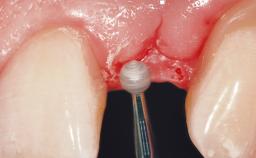

A 30-year-old female patient was referred to the office for the treatment of tooth 11. Her chief concern at the initial visit was to inquire, “Why is my tooth pink?” Upon clinical examination, it was determined that tooth 11 had a previous history of trauma and that the clinical crown had become noticeably pink in color as a result of internal resorption. This diagnosis was confirmed radiographically, indicating a large radiolucency involving the central and distal portions of the clinical crown. It was determined that restoration of this tooth was not possible, and that extraction was indicated. The presence of a mid-line diastema, which the patient wanted to reproduce, directed the treatment plan for tooth replacement utilizing a dental implant.

Soft Tissue Grafting None

Soft Tissue Anatomy Intact Defective

Soft Tissue Contour and Volume Ideal